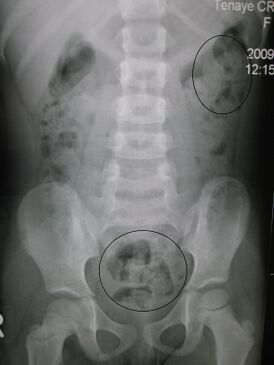

Рентгенограмма запора у малолетнего ребёнка. Кругами отмечены каловые массы (фекалии — белым цветом, окружающий их кишечный газ — чёрным цветом)Рентгенограмма запора у малолетнего ребёнка. Кругами отмечены каловые массы (фекалии — белым цветом, окружающий их кишечный газ — чёрным цветом)